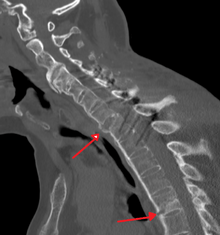

Fracture of the T5 and C7 vertebra due to trauma in a person with ankylosing spondylitis as seen on a CT scan

Prognosis is related to disease severity.[7] AS can range from mild to progressively debilitating and from medically controlled to refractory. Some cases may have times of active inflammation followed by times of remission resulting in minimal disability while others never have times of remission and have acute inflammation and pain, leading to significant disability.[7] As the disease progresses, it can cause the vertebrae and the lumbosacral joint to ossify, resulting in the fusion of the spine.[24] This places the spine in a vulnerable state because it becomes one bone, which causes it to lose its range of motion as well as putting it at risk for spinal fractures. This not only limits mobility but reduces the affected person's quality of life. Complete fusion of the spine can lead to a reduced range of motion and increased pain, as well as total joint destruction which could lead to a joint replacement.[25]

Osteoporosis is common in ankylosing spondylitis, both from chronic systemic inflammation and decreased mobility resulting from AS. Over a long-term period, osteopenia or osteoporosis of the AP spine may occur, causing eventual compression fractures and a back "hump".[26] Hyperkyphosis from ankylosing spondylitis can also lead to impairment in mobility and balance, as well as impaired peripheral vision, which increases the risk of falls which can cause fracture of already-fragile vertebrae.[26] Typical signs of progressed AS are the visible formation of syndesmophytes on X-rays and abnormal bone outgrowths similar to osteophytes affecting the spine. In compression fractures of the vertebrae, paresthesia is a complication due to the inflammation of the tissue surrounding nerves.